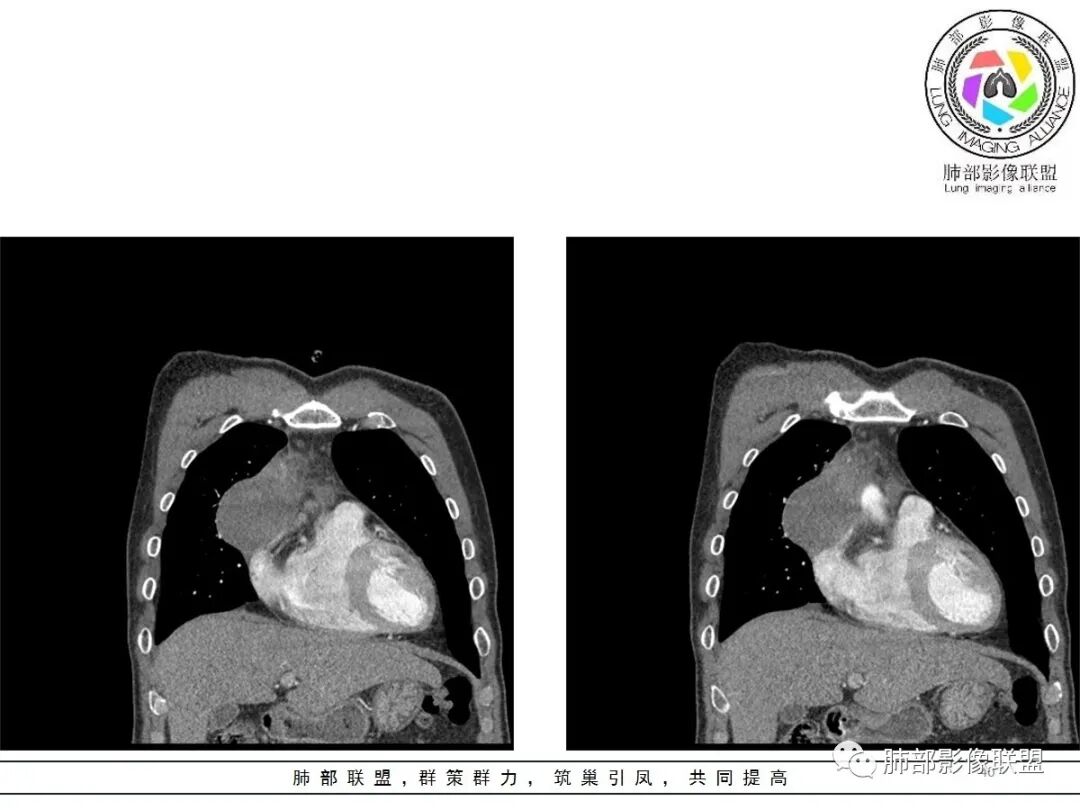

小赵:这个是3月15日的视频

小赵:第二个是3月19日的视频

周围脂肪间隙密度增高,内部小点状很低密度影

右侧少量胸水

19日,4天后, 内部低密度影有,周围渗出增多,胸水增多

薄膜状强化

影像上周围病灶变化明显

常规肿瘤侵犯不支持,太快

应该是炎性病变渗出

脂肪密度明显,还有钙化、囊性病变,支持含脂质类病变破裂

周围是化学性炎症或出血所致

后期强化,可能与炎症有关

2.胸膜掀起,右侧内乳动脉略增粗,定位右前上纵隔内占位。

3.右上纵隔囊实性占位,边界清楚。中央见点状脂肪密度影,边缘见一点状钙化影,增强不均匀环形强化。

4.四天内病灶变化快,块影增大且不规则,包膜似不完整,边界不清,上份可见浸润或渗出,与周围心脏大血管及心包等间隙不清。胸水增多。

5.未见明显淋巴结增大

第一次的检查符合胸腺瘤影像学改变,短期内的形态学改变及突然出现的边界模糊或浸润等,符合出血或炎症。